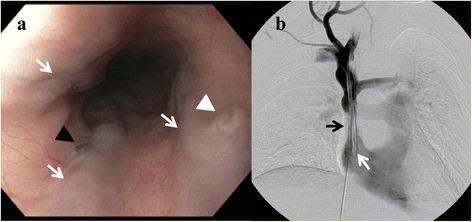

CASE PRESENTATION

A young woman with a benign superior vena cava stenosis due to a tunneled internal jugular vein dialysis catheter presented with hematemesis and melena. Urgent upper endoscopy revealed multiple 'downhill' esophageal varices with stigmata of recent hemorrhage. As there was no active bleeding, no endoscopic intervention was performed. CT angiography demonstrated stenosis of the SVC surrounding the distal tip of her indwelling hemodialysis catheter. The patient underwent balloon angioplasty of the stenotic SVC segment with resolution of her bleeding and clinical stabilization.

一名年轻女性因隧道式颈内静脉透析导管导致良性上腔静脉狭窄,出现呕血和黑便。紧急上消化道内镜检查发现多处“下行性”食管静脉曲张并有近期出血迹象。由于没有活动性出血,未进行内镜干预。CT血管造影显示其留置血液透析导管远端周围的SVC狭窄。患者接受了狭窄SVC段的球囊血管成形术,出血得到缓解,临床症状稳定。